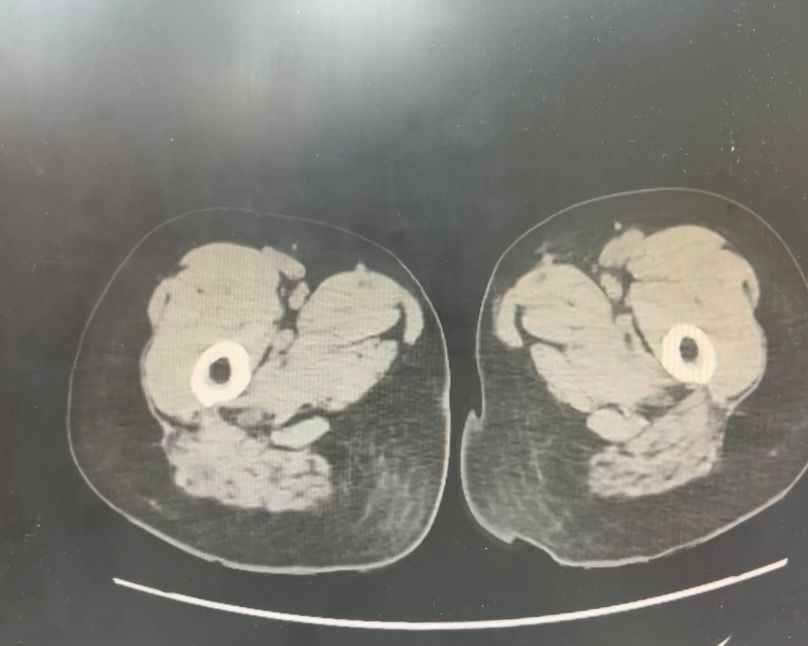

복부 ct (contrast) 영상 판독해주세요!!

어제 복부 ct 촬영하였는데 판독 하려면 시간이 걸려서 미리 알 수 있을까요? 지금 증상은 윗배가 많이 나왔고 허리 아프고 조금만 밥 먹어도 배부른 상태입니다..

• 1번 째 사진

어제 말씀드린대로 자궁 쪽에 불규칙한 음영들이 보이고 있어 물혹이 있는 것으로 의심해 볼 수 있으며, 이외에 복부에 가스가 조금 차있거나 비장이 약간 커져 있는 듯한 모습이 보이나 일부 단면만으로 유추한 것이라 판독 상 틀릴 가능성도 있겠습니다.